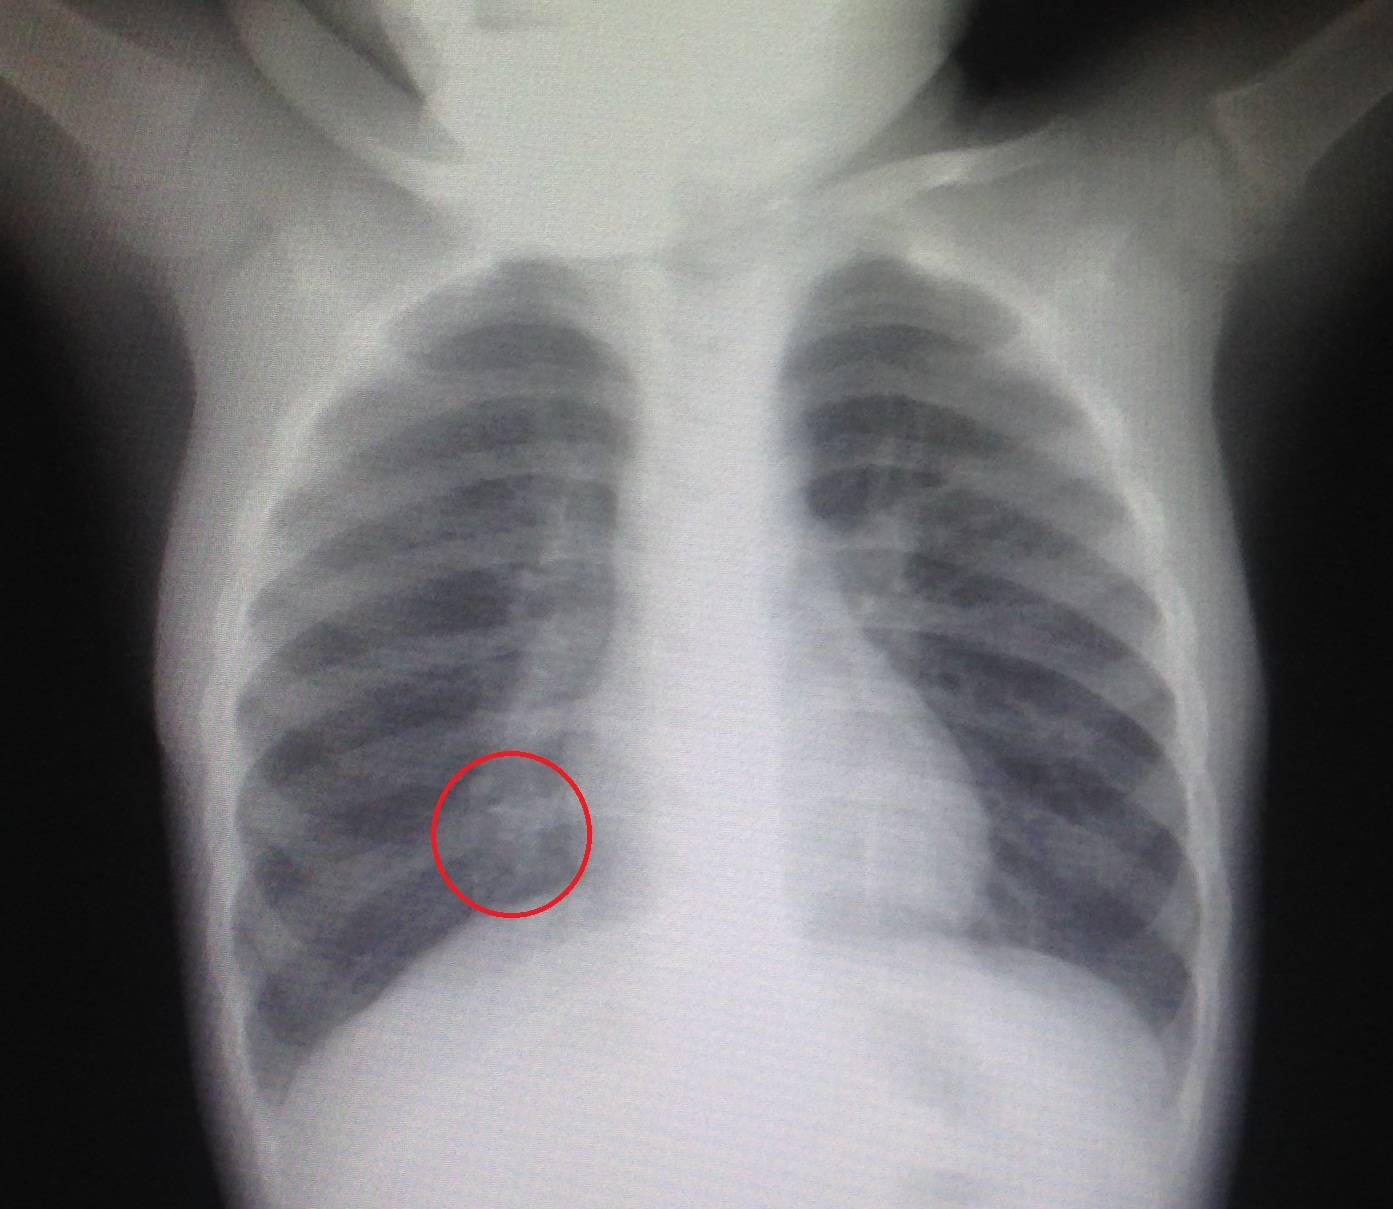

Как видно из таблицы, и лабораторные исследования не дают спорные результаты, поэтому для установки окончательного диагноза используют рентгенографию легких. Рентгеновский снимок легких показывает признаки пневмонии у грудничков и старших детей — участки инфильтрации легочной ткани и их размер.

На фото участок легкого пораженный воспалительным процессом

Исходя из области поражения легкого, врач определяет тип пневмонии:

- долевая – поражена доля легкого;

- сегментарная – сегмент легкого;

- полисегментарная – несколько сегментов;

- очаговая – группы альвеол;

- бронхопневмония – затронута часть легочной ткани и бронхи;

- интерстициальная – интерстициальная ткань.